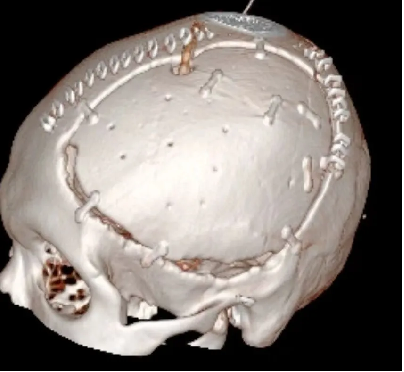

术后: